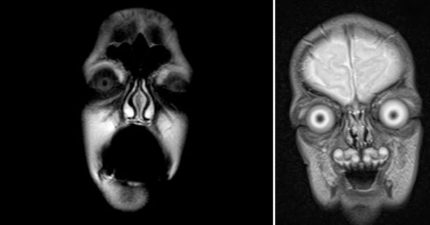

當你在做MRI核磁共振的時候,一個很可怕的事情會發生。